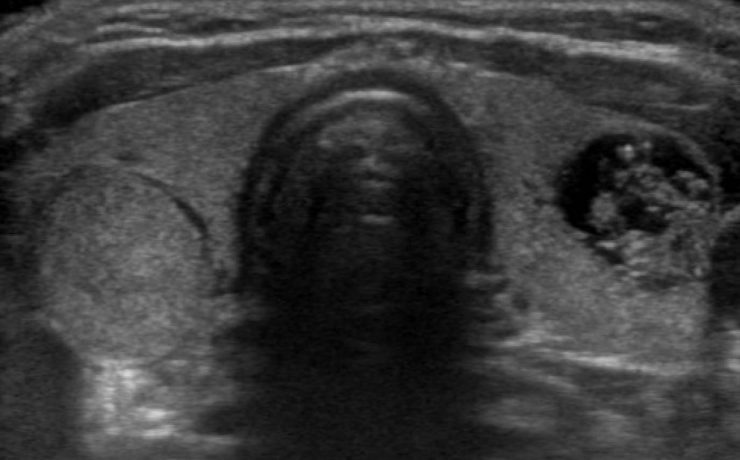

DIAGNOSTICO ECOGRÁFICO PRENATAL DE HEPATOBLASTOMA.

Las lesiones focales en el hígado en niños de 0 a 3 años incluyen neoplasias, lesiones metastásicas, masas inflamatorias y quistes (congénitos o adquiridos); las neoplasias primarias tanto benignas como malignas representan 1 a 2% de todos los tumores pediátricos. El hepatoblastoma es el tumor hepático maligno más frecuente en